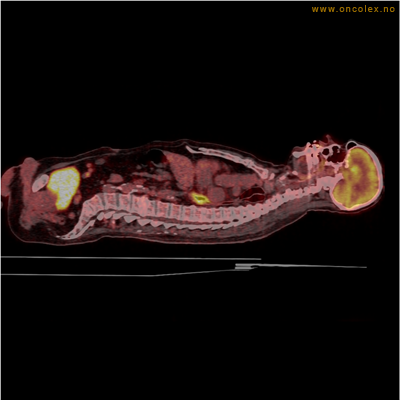

Eksempler på funn

Vev som tar opp mer radioaktivt stoff, synes som hvite områder som lyser opp mer i forhold til annet vev som tar opp mindre sukker.